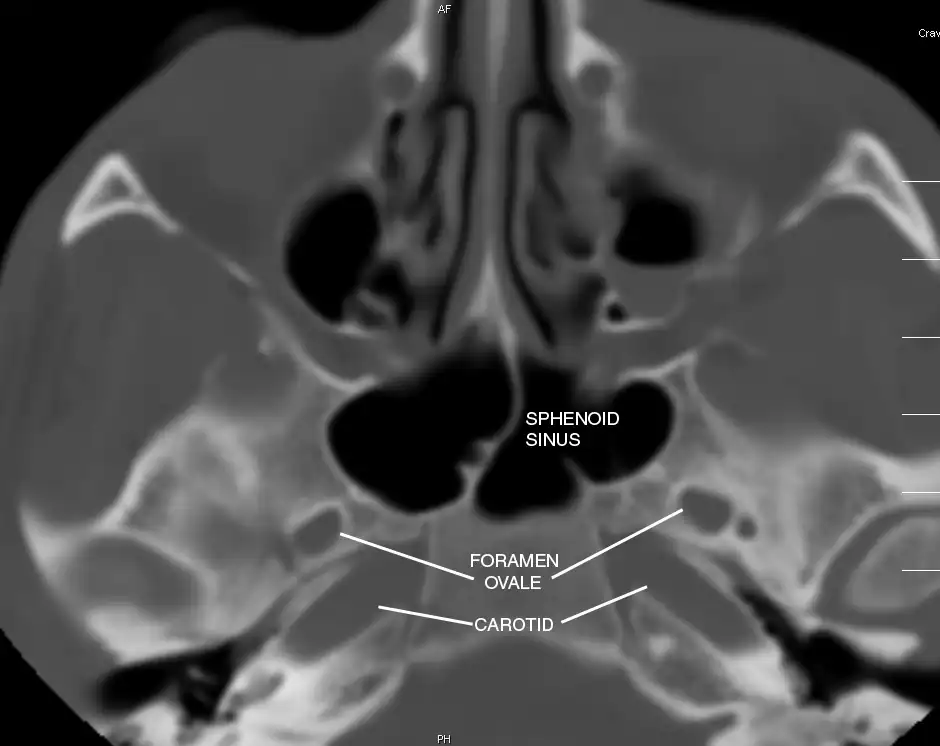

Sphenoid Sinus has 12 close structures: II, III, IV, V1, V2, VI, Vidian Nerve, Carotid artery, Brain, Dura, Pituitary.

- V2 = Maxillary division, Trigeminal Nerve: exits foramen rotundum, superomedial to V3's foramen ovale.

- C = Carotid Artery: often with bony dehiscence into sphenoid. Together with CN II forms opticocarotid recess.